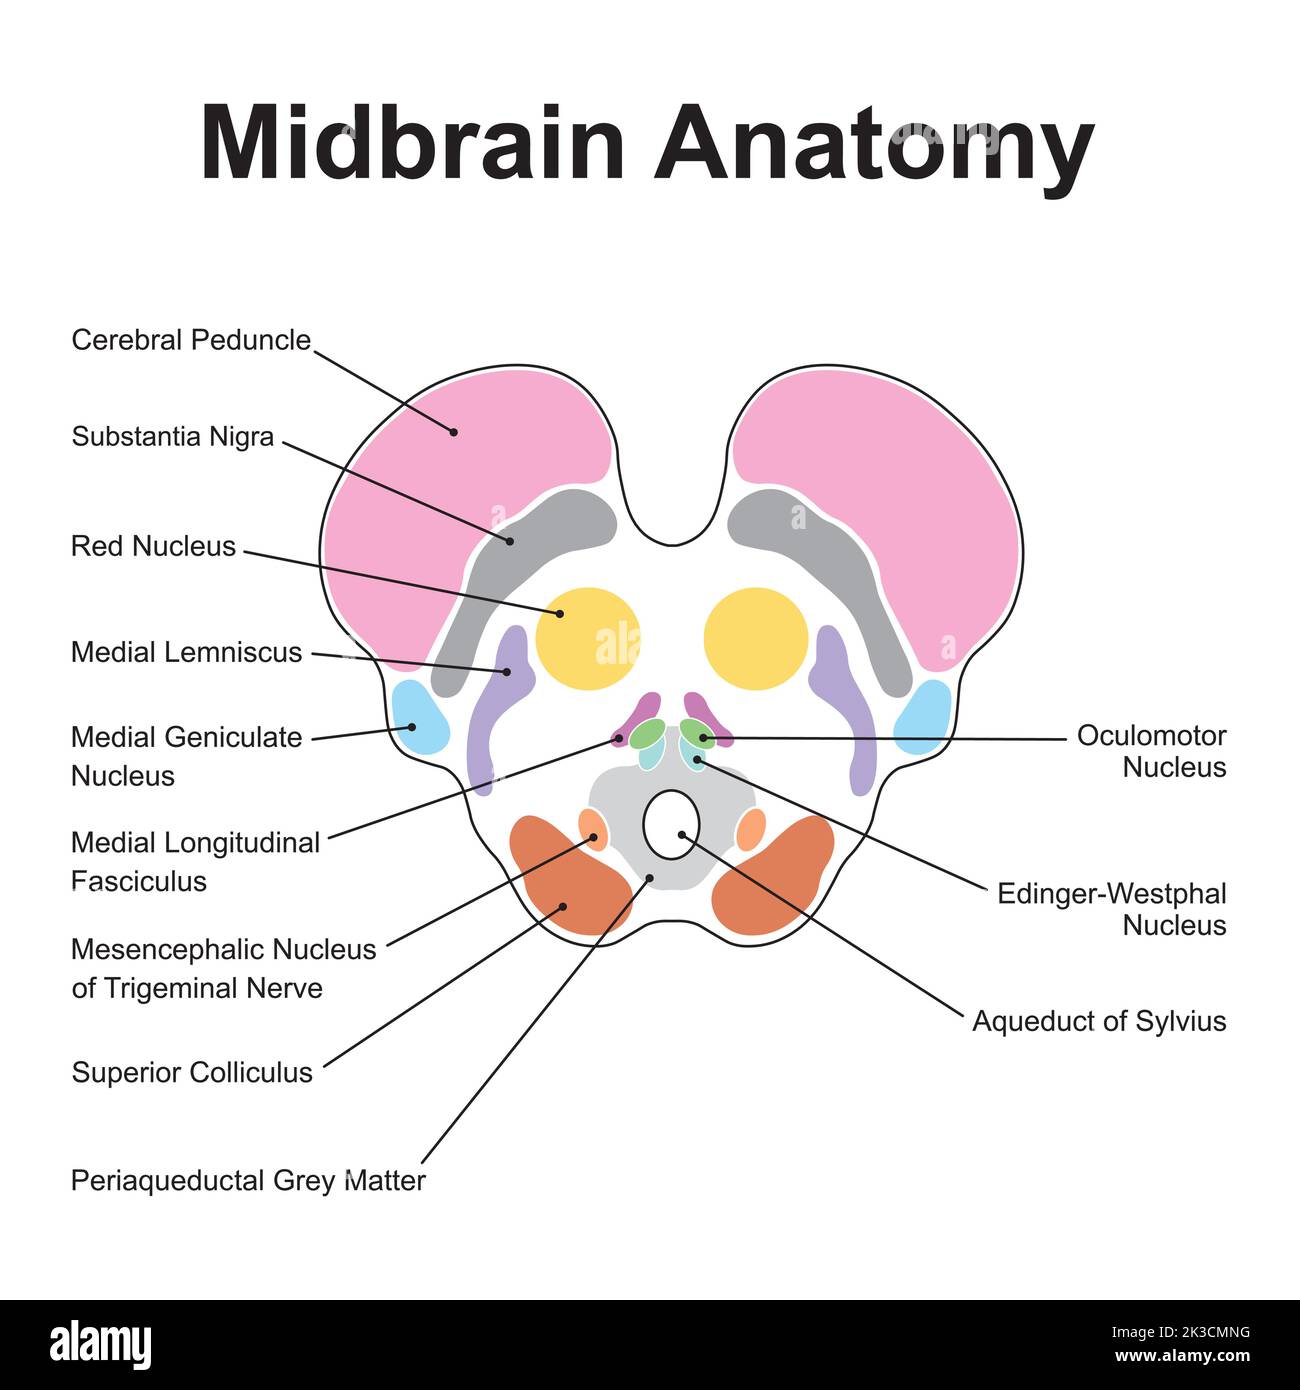

RF2K3CMNG–Progettazione scientifica dell'anatomia del midbrain. Sezione assiale a livello del collicolo superiore. Simboli colorati. Illustrazione vettoriale.

RF2K3CMHJ–Progettazione scientifica dell'anatomia del midbrain. Sezione assiale a livello del collicolo superiore. Simboli colorati. Illustrazione vettoriale.